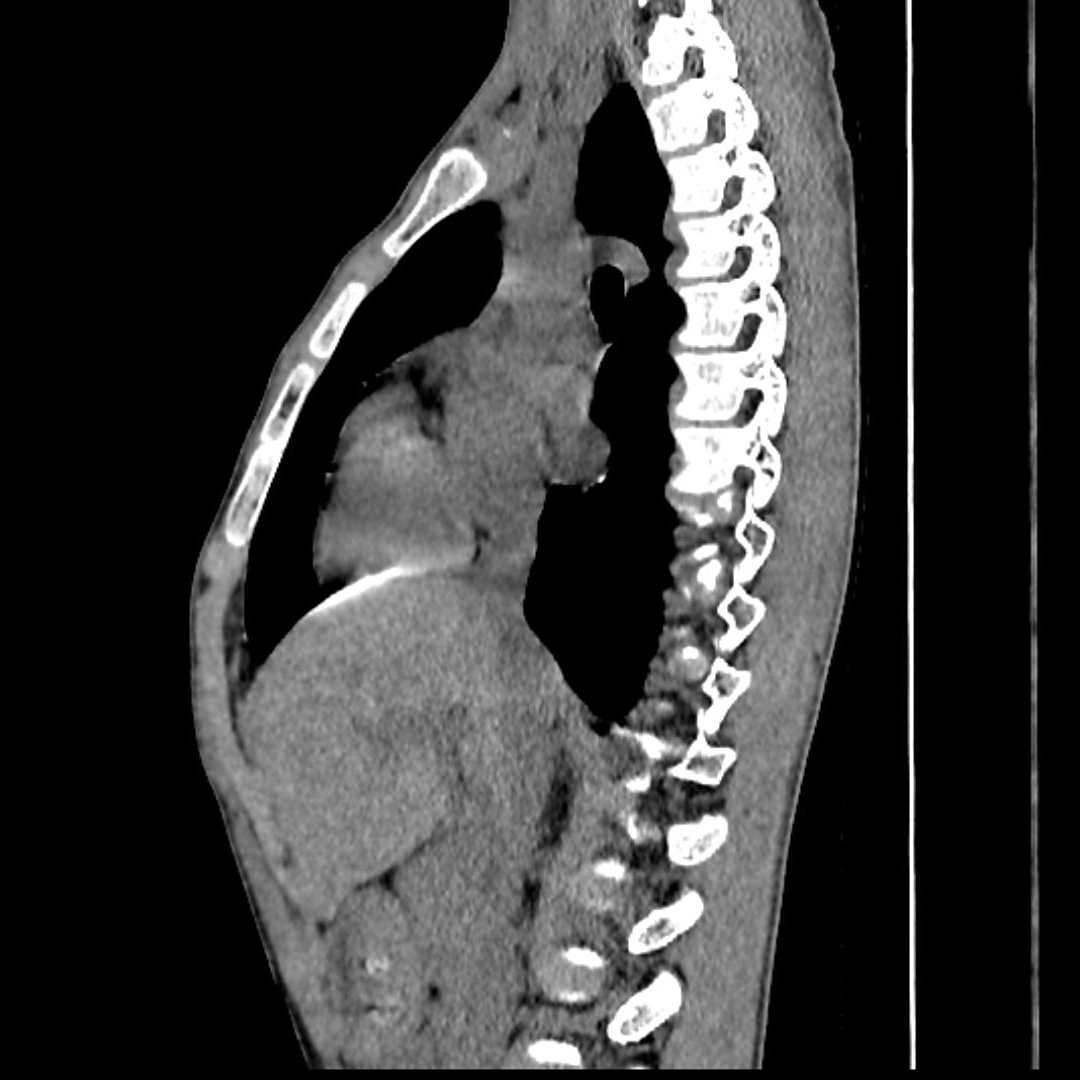

该患者为男性,17岁,身高183,胸廓前后径缩短,中间明显凹陷,诊断为扁平